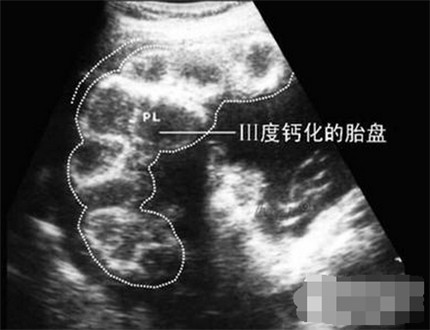

胎盘的成熟度共分四级: o 级, 1 级, 2 级和 3 级

1级标志胎盘基本成熟;

2级晚标志胎盘成熟;

3级晚标志胎盘已衰老,由于钙化和纤维素沉着,使胎盘输布氧气及营养物质的能力降低,胎儿随使有危险。

胎盘成熟度是指胎盘的老化程度,成熟程度越低说明胎盘的功能越好,能为宝宝提供的营养也越多,反而越到后期,胎盘老化到了2级、3级甚至钙化了,给宝宝提供的能量和氧气就会越来越少,会引起宫内窘迫等状况。